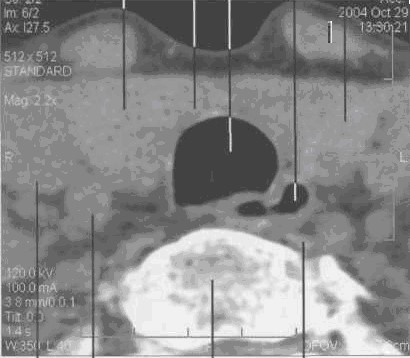

Компьютерная томография ЩЖ

КТ железы проводится от яремной вырезки до уровня Су. Толщина среза -- 8 мм, шаг -- 4--8 мм. Обычное положение неизмененной железы -- на 2 см выше верхнего края гру­дины.

Форма -- в виде двух овалов с относительно ровными контурами, хорошо отграниченными от окружающих тканей.

Поперечные размеры составляют 30x20 мм, высота -- 30--40 мм.

Структура -- однородная. Денситометрическая плотность (при содержании в паренхиме железы 0,65 мг/г йода) -- 70+10 HU.

Кпереди от железы визуализируются грудино-щитовидные и грудино-подъязычные мыш­цы, по передней поверхности которых проходят наружные яремные вены.

Латеральной поверхностью железа прилежит к внутренней яремной вене и сонной арте­рии. Слева сонная артерия лежит под веной, справа проходит ближе к телу позвонка по задне-латеральной поверхности железы.

По заднемедиальному краю щитовидной железы, кзади от трахеи располагаются паращитовидные железы, которые могут быть видны у тучных пациентов. Паращитовидные желе­зы могут визуализироваться между собственной капсулой железы и жировой клетчаткой. Число паращитовидных желез колеблется от 2--4 до 5--6. Их длина составляет 5--6 мм, толщина -- около 4 мм.

Задний край щитовидной железы отделен от тел пятого и шестого шейных позвонков длин­ной мышцей шеи. В центре среза между трахеей и серединой тел позвонков располагается пи­щевод (рис. 28)

Рис. 28. Серия КТ изображений щитовидной железы на разных уровнях щитовидного хряща в аксиальной плоскости.